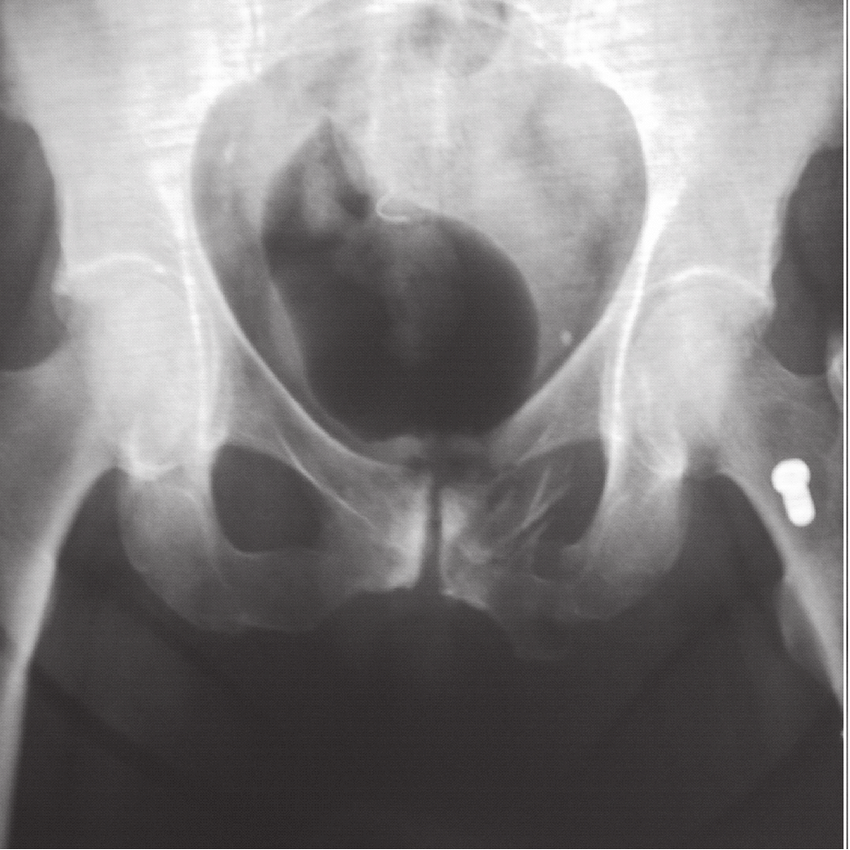

Lo pone en la interconsulta y le solicitan una radiografía de pelvis y cadera que nadie le había hecho hasta entonces:

Din, din, premio: fractura de rama isquiopúbica

Fue algo muy similar a esto, pero solamente fractura de una rama y no descargué la RX original al no tratarse de un caso objeto de exposición a congreso/artículo y un poco también por preservar la intimidad del paciente puesto que el caso iba más sobre el manejo.